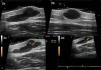

HRDU with a 22-MHz probe (MyLab Class C, Esaote) revealed a well-defined anechoic image in the dermis and hypodermis. The image was round in the longitudinal plane and polylobulated in the transverse plane. It was 4.2mm thick and had an internal septum measuring 11.9mm on the transverse axis and 5.9mm on its longitudinal axis. Posterior enhancement was observed. Power Doppler mode revealed sparse intralesional vascularization, with low-flow venous and arterial vessels measuring 0.2 to 0.4mm in diameter; spectral Doppler mode revealed that the arterial vessels had a maximum systolic peak of 2.2cm/s (Fig. 2). The ultrasound characteristics led us to suspect a benign subcutaneous tumor or hematoma. However, given the time since onset and the patient's symptoms, the tumor margins were determined using ultrasound, and the lesion was surgically removed.

High-resolution ultrasound with a 22-MHz probe (MyLab class C, Esaote) reveals a well-defined polylobulated anechoic image with an internal septum located in the dermis and hypodermis. Positive enhancement was observed. The image measured 11.9mm along its transverse axis (A) and 5.9mm along its longitudinal axis (B). Power Doppler revealed sparse intralesional vascularization with arterial and venous vessels measuring between 0.2 and 0.4mm in diameter (C). Spectral Doppler showed that the arterial vessels had a maximum systolic peak of 2.2cm/s (D).